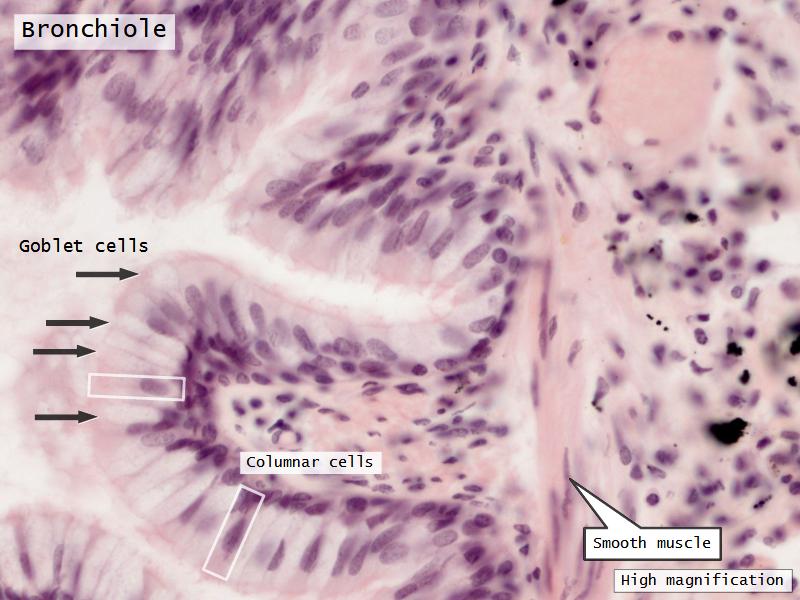

- Bronchioles

- Smooth muscle REPLACE cartilage

- Ciliated columnar > Ciliated cuboidal

- NO glands - goblet cells -> secretory cells